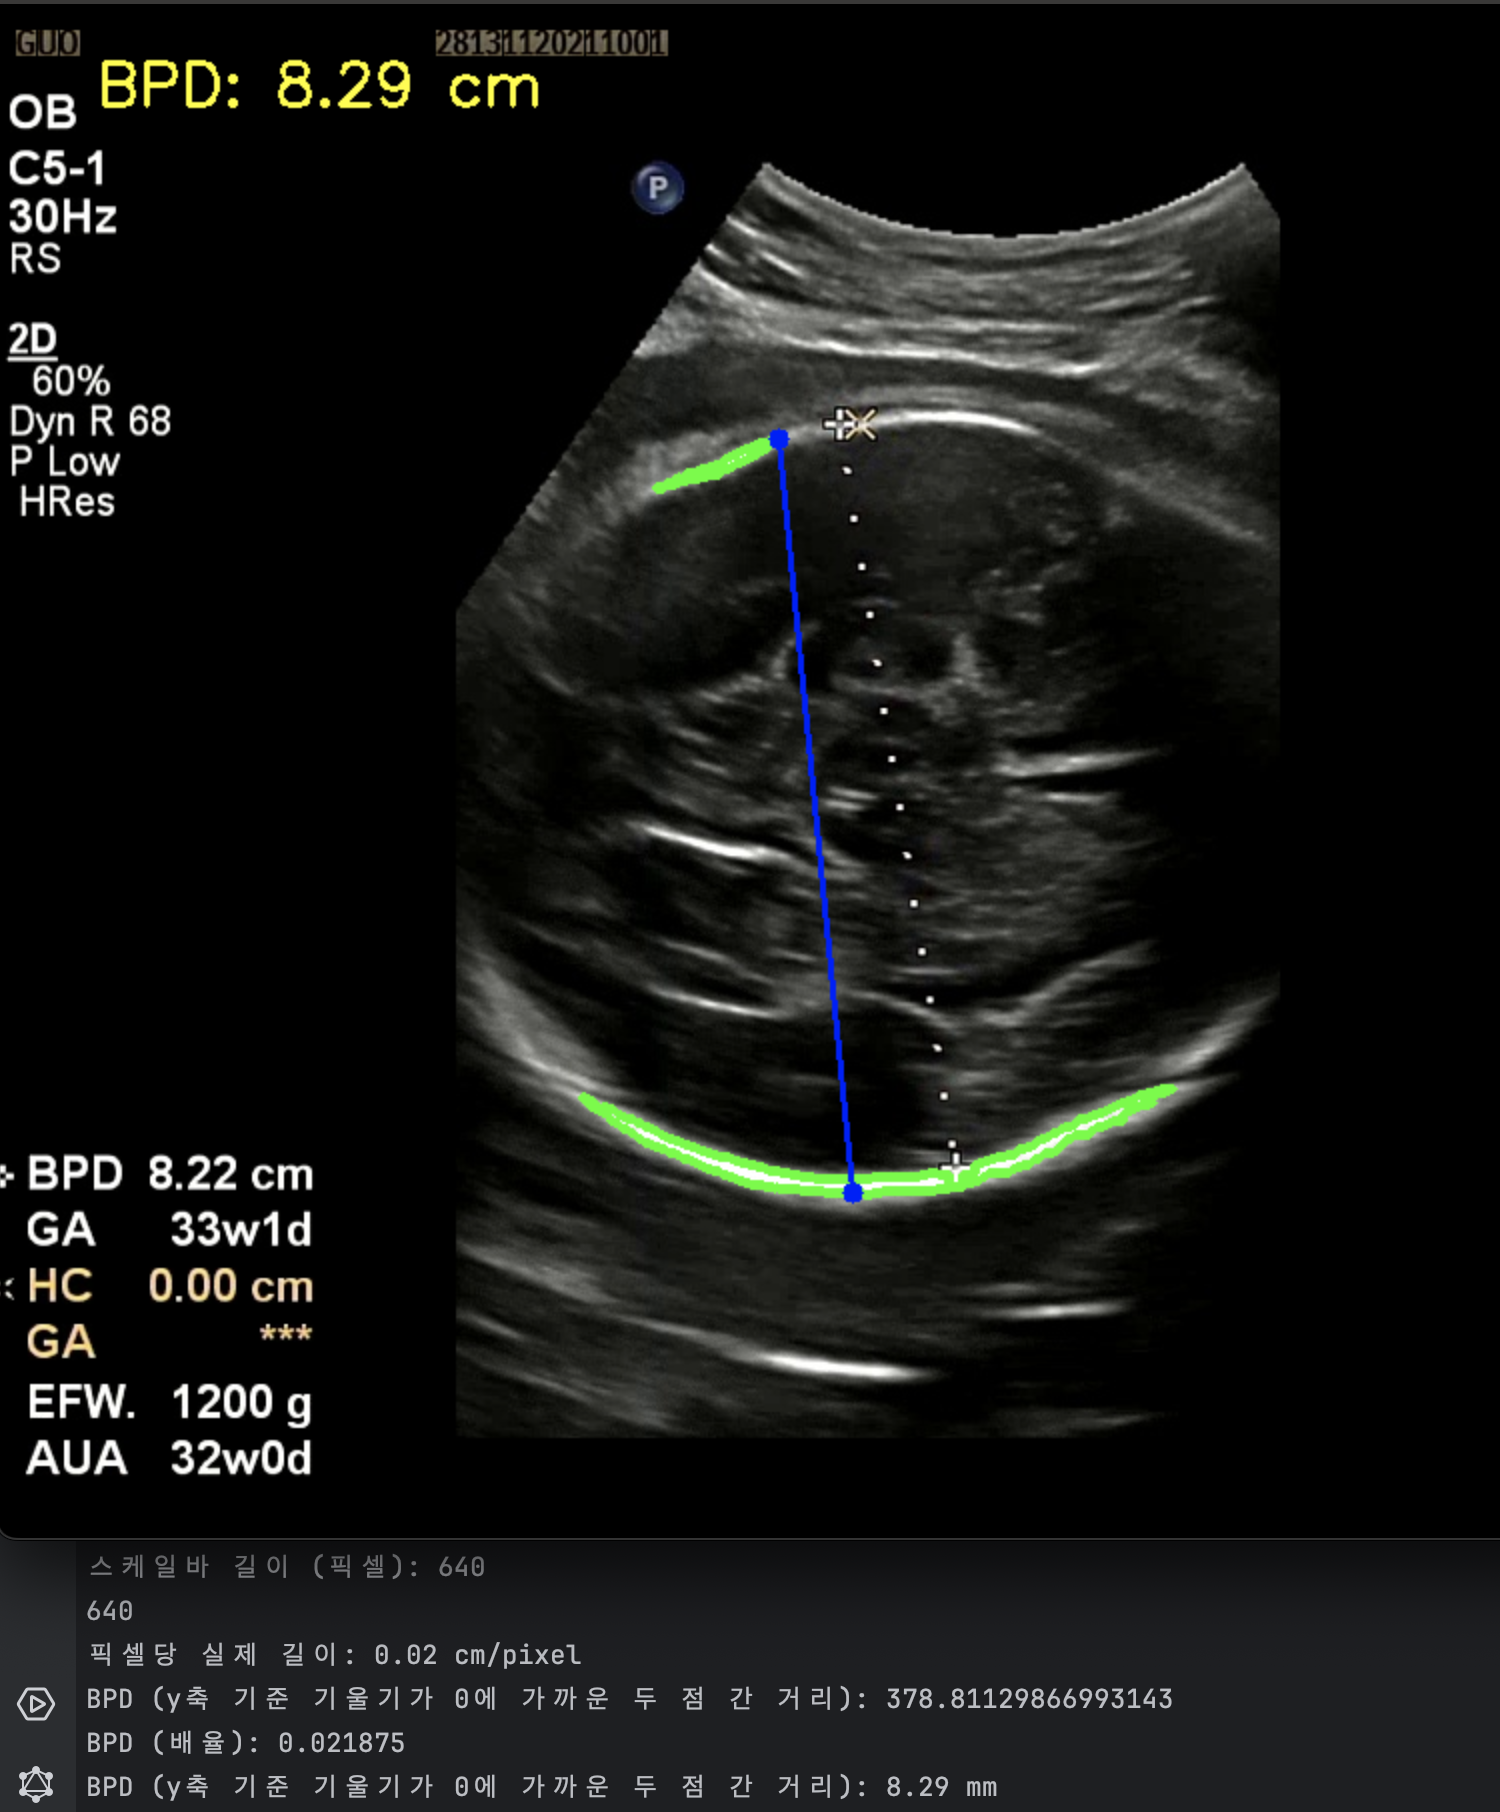

대부분의 녹화본에는 스케일바가 있다. 여기서 픽셀 당 실제거리 (cm/pixel) 을 구할 수 있다고 판단했다. 그래서 내가 원하는 두 점 사이의 거리 (단순 픽셀 거리) 곱하기 cm/pixel 을 곱하면 실제 거리를 구할 수 있다고 생각했다. cm/pixel 이 배율인 셈이다.

실제로는 8.22 cm 로 기록되었고 내가 측정한 기록값은 8.29 cm 로 오차는 크지 않았다. 가설을 검증했고 충분히 해볼 만하고 생각했다. 다만 아래와 같은 해결 과제가 남았다. 첫 번째는 계산 시 (14 cm / 스케일 바 픽셀 거리) 로 하드코딩해서 배율을 계산했기 때문에 스케일 바를 검출하는 이미지 전처리 과정이 필요했다. 두 번째는 초록색 영역 검출 시 곡선과 같은 형태 두 개를 찾고 그 사이 거리를 찾는 식이라 이미지별로 다소 편차가 있었다. 내 눈에는 원처럼 보이는데 컴퓨터가 인식할 때는 원으로 인식하지 않아서 반원 곡선 형태를 찾도록 코딩했다.